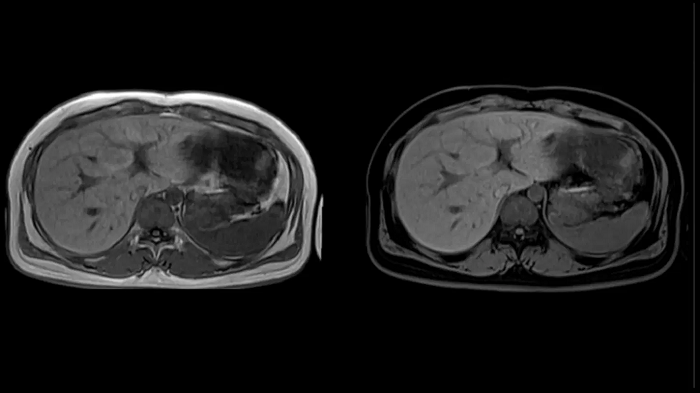

Abdomen

T1 VIBE Dixon with CAIPIRINHA

Get benefitted from Siemens Healthineers dedicated CAIPIRINHA acceleration to gain a complete abdominal volume within a single breath-hold. The Dixon technique offers outstanding fat water separation for a flawless representation of the abdominal anatomy.

MAC-ID: 7aaaa0165.

MAC-ID: 7aaaa0165. Image Credit: Siemens Healthineers